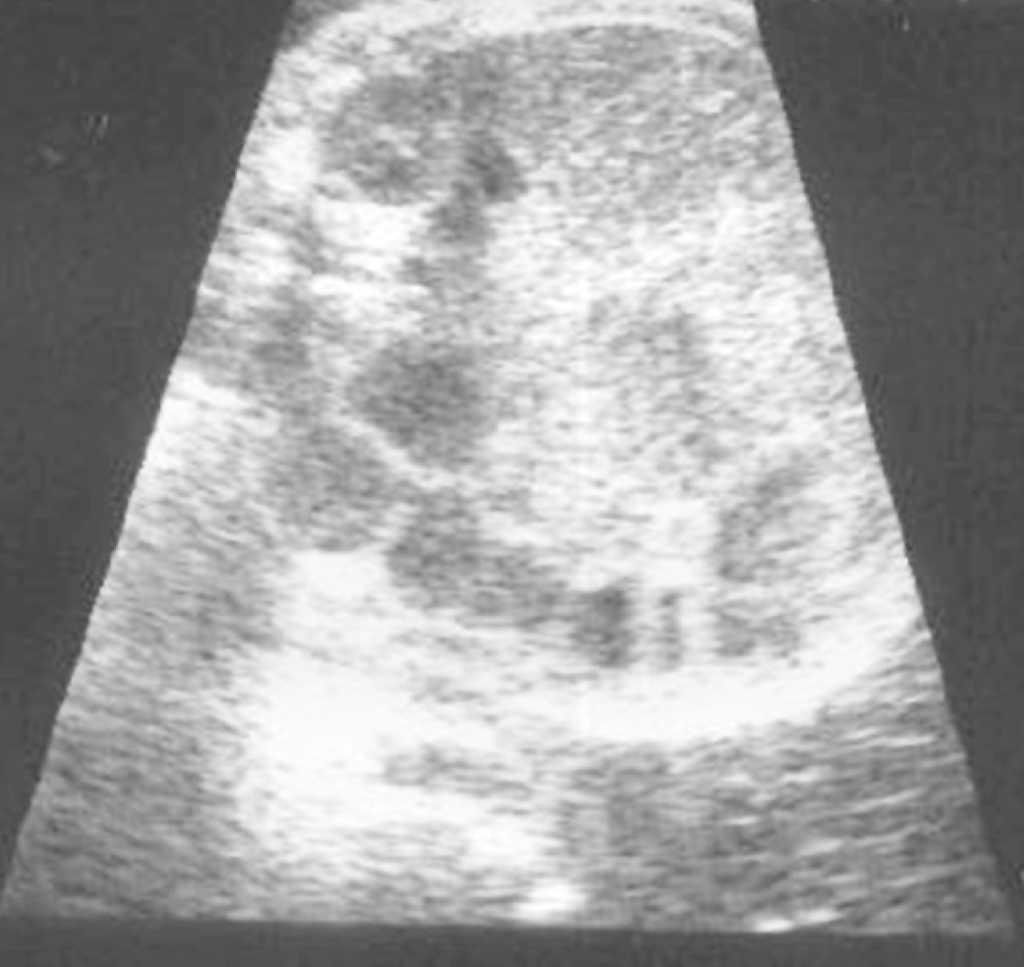

En un primer estudio ecográfico, practicado en la semana 32 + 2, destaca un circunferencia abdominal fetal (CAF) mayor al percentil 95 y un polihidramnios con índice de líquido amniótico (ILA) de 23. En el hemiabdomen inferior se visualiza una tumoración redondeada de aspecto quístico, desde la vejiga al borde hepático, de 59 x 48 x 46 mm de diámetro, con nivel líquido-sólido, compatible con quiste ovárico fetal, con parte sólida avascular (figs. 1 y 2). Las asas intestinales distales se encontraban dilatadas, con peristaltismo y rechazadas en hemiabdomen izquierdo probablemente por compresión extrínseca (fig. 3). No se visualiza líquido libre ni calcificaciones. El resto de la exploración ecográfica se encontraba dentro de la normalidad.

Figura 1.Corte sagital de abdomen fetal con formaciones anecoicas con contenido ecogénico en su porción declive.